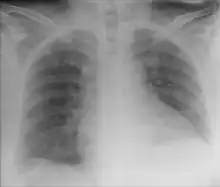

Chest X-ray showing obvious Chilaiditi's sign, or presence of gas in the right colic angle between the liver and right hemidiaphragm. | |

Chilaiditi syndrome is a rare condition when pain occurs due to transposition of a loop of large intestine (usually transverse colon) in between the diaphragm and the liver, visible on plain abdominal X-ray or chest X-ray.[1]

Normally this causes no symptoms, and this is called Chilaiditi's sign. The sign can be permanently present, or sporadically. This anatomical variant is sometimes mistaken for the more serious condition of having air under the diaphragm (pneumoperitoneum) which is usually an indication of bowel perforation, possibly leading to surgical interventions.